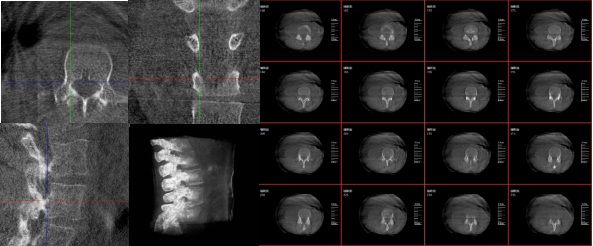

三維重建技術(shù)在醫(yī)學(xué)影像診斷領(lǐng)域十分重要,它是一種利用計(jì)算機(jī)軟件將二維醫(yī)學(xué)影像(如X光、CT、MRI等)轉(zhuǎn)化為三維立體圖像的技術(shù),可以為醫(yī)生提供更直觀、更清晰的圖像信息,方便醫(yī)生從多個(gè)角度觀察病灶,從而更全面地了解病情,有助于提高診斷的準(zhǔn)確性和效率。

三維重建技術(shù)在醫(yī)學(xué)影像診斷中的應(yīng)用非常廣泛,主要包括以下幾個(gè)方面:

1.診斷疾?。和ㄟ^(guò)三維重建技術(shù),醫(yī)生可以更直觀、清晰地觀察到患者體內(nèi)的異常情況,如腫瘤、骨折等,從而更準(zhǔn)確地診斷疾病。

2.手術(shù)規(guī)劃:在手術(shù)前,醫(yī)生可以通過(guò)三維重建技術(shù)對(duì)患者的病變部位進(jìn)行詳細(xì)的觀察和分析,制定出最佳的手術(shù)方案。

3.手術(shù)導(dǎo)航:在手術(shù)過(guò)程中,醫(yī)生可以通過(guò)三維重建技術(shù)實(shí)時(shí)觀察手術(shù)器械的位置,提高手術(shù)的精確性和安全性。例如在關(guān)節(jié)外科手術(shù)中,存在植入物的錯(cuò)位在術(shù)中不易發(fā)現(xiàn)的情況,如果在術(shù)后CT中檢查出,就不可避免地需要翻修手術(shù),這就會(huì)增加并發(fā)癥的概率以及感染風(fēng)險(xiǎn)。而通過(guò)術(shù)中三維影像設(shè)備PLX C7600的檢查,可以立即發(fā)現(xiàn)植入物的錯(cuò)位,減少不必要的第二次手術(shù)。